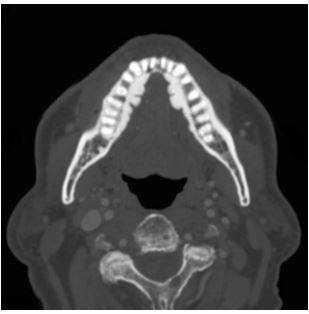

- МСКТ челюсти. На начальных стадиях процесса выявляются «пустые» костные лунки, очаги деструкции челюсти, уменьшение размера периодонтальной щели. Для поздней стадии остеонекроза характерен масштабный очаг деструкции, который выходит за границы альвеолярного отдела челюстной кости. Изредка определяются патологические переломы челюсти.

Рентген, а лучше КТ (компьютерная томография) помогает определить площадь патологического процесса, степень поражения, наличие переломов, секвестров (отмерших фрагментов кости, свободно лежащих между здоровых тканей).